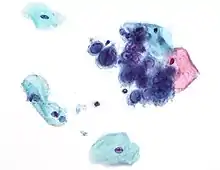

If the mother has active herpes simplex (as may be suggested by a pap test), delivery by Caesarean section can prevent the newborn from contact, and consequent infection, with this virus.